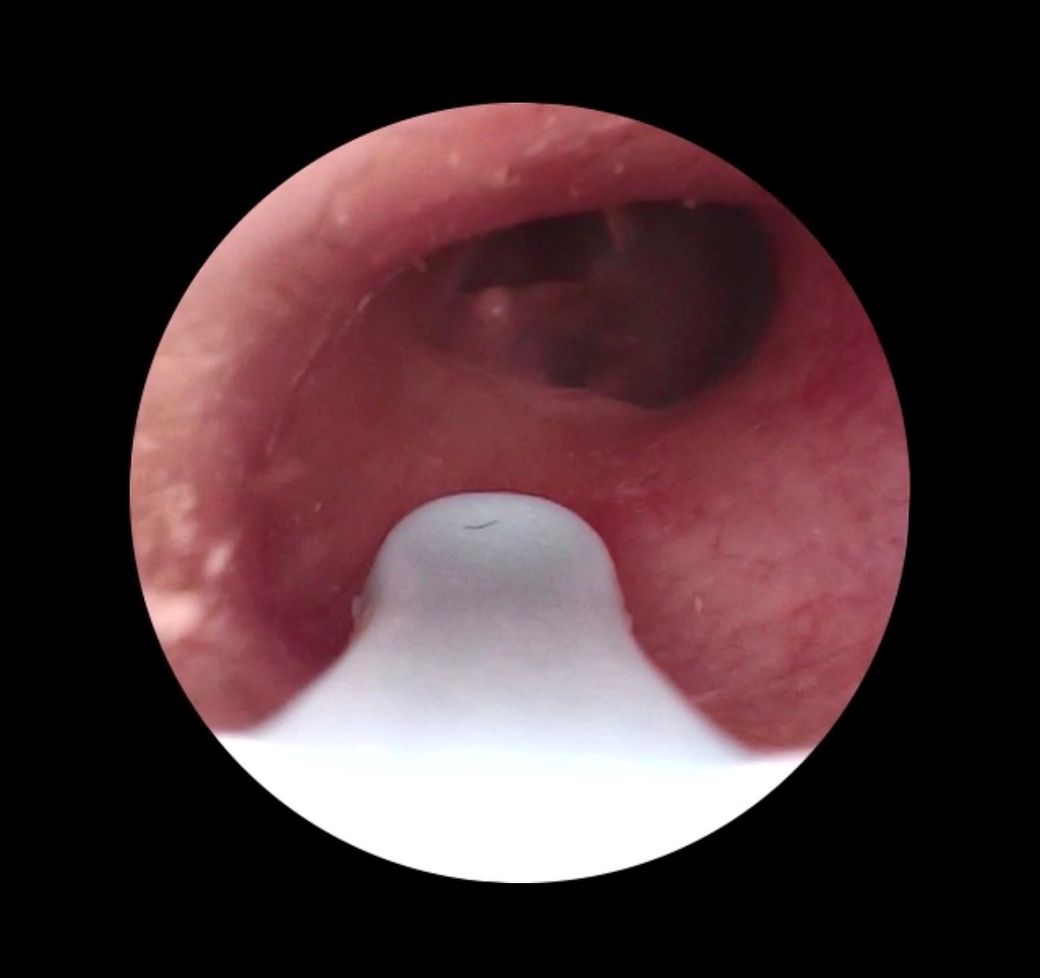

내시경 귀이개가 있어서 오른쪽 귀를 봤는데 막이 보이는데 구멍이 보여서 천공이 생긴걸까요?

왼쪽 귀에는 저런게 안보였던거 같고 1주 전에 공연용 스피커앞에 오래있어 몇시간동안 오른쪽 귀가 먹먹했었습니다. 현재는 아무런 불편함을 느끼진 않습니다

• 사진에서 보이는 구조는 고막 자체라기보다는 외이도 깊은 부분에 고막이 비스듬히 보이는 장면으로 보입니다. 중앙 상부에 보이는 어둡게 보이는 부분은 고막의 얇은 부위(pars flaccida)나 빛 반사, 또는 촬영 각도에 따른 음영일 가능성이 있습니다. 사진 한 장만으로는 고막 천공(tympanic membrane perforation)을 확정하기는 어렵지만, 전형적인 천공처럼 고막 전체를 관통하는 뚜렷한 결손 형태로 보이지는 않습니다.